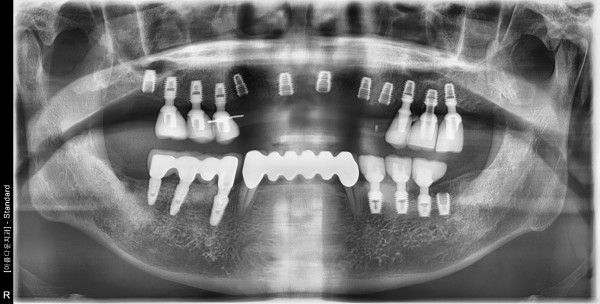

67세 남자환자/ 상하악 구치부 및 상악전치 뼈이식, 임플란트식립 (완성)